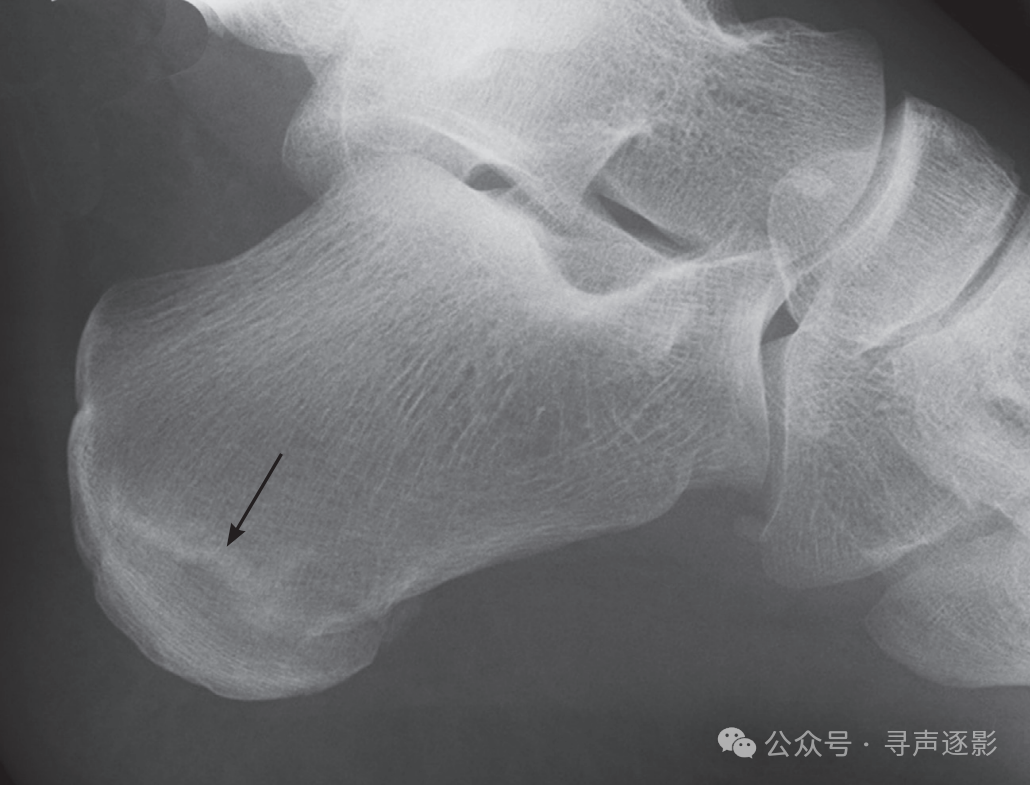

骨软骨骨折表现为局限性缺损(即透亮区)或皮质面不规则,通常位于距骨穹顶的内侧或外侧。有时可见小碎骨片自穹顶剥脱,游离于关节腔内。

左图:距骨颈骨折,移位(箭头)。右图:距骨颈骨折,无移位(箭头)。